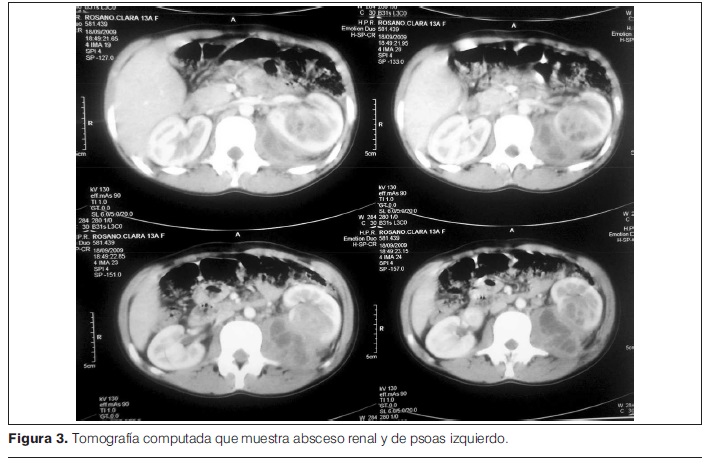

Tomografía computada (TC) realizada en HP-CHPR, que muestra absceso renal y de psoas izquierdo, con derrame pleural ipsilateral (figura 3).

Con diagnóstico de absceso renal y de psoas, se realiza drenaje percutáneo guiado por ecografía, obteniéndose 60 ml de líquido hematopurulento.